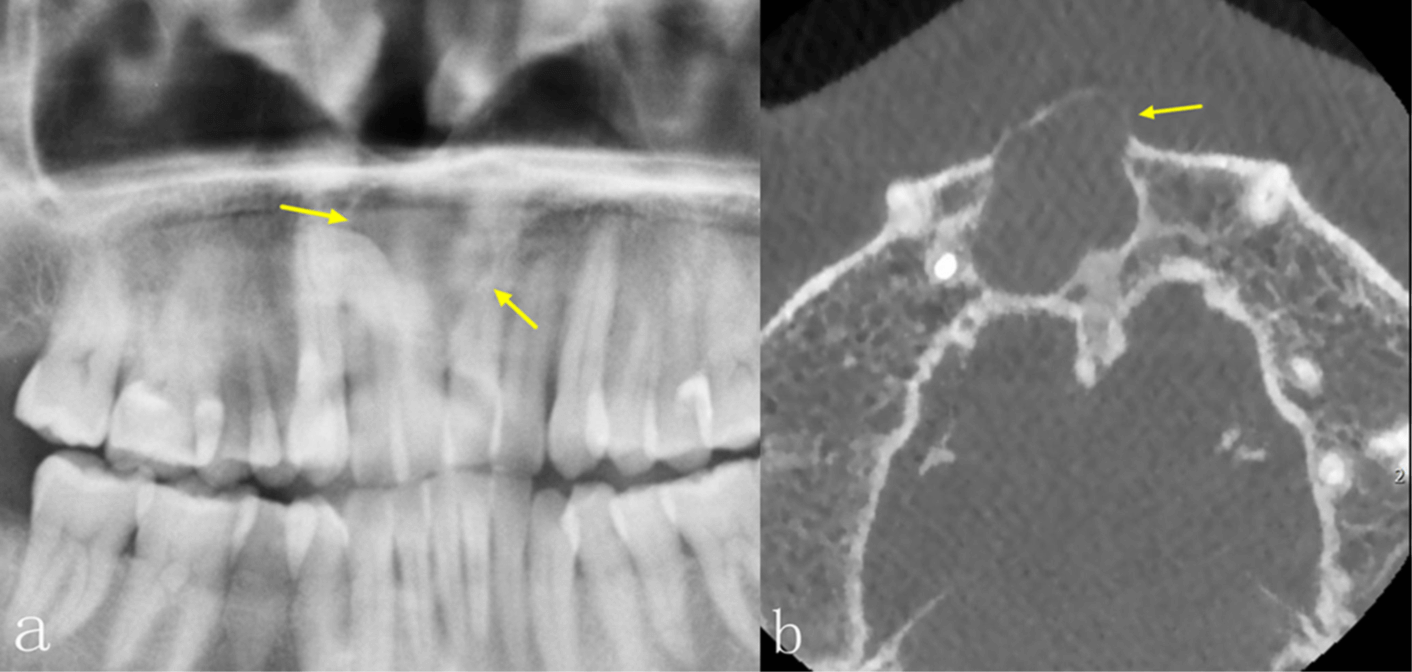

La radiografía panorámica (PAN) y la tomografía computarizada de haz cónico (TCCB) son dos modalidades radiográficas utilizadas en el diagnóstico, la planificación del tratamiento y el manejo de las enfermedades orales y maxilofaciales. No solo muestran las características de las lesiones en las imágenes, sino que también guían a los médicos para que realicen los diagnósticos más adecuados, así como los planes de tratamiento posteriores, y para supervisar la curación y/o la recurrencia de la enfermedad durante el seguimiento. La PAN, como técnica de imagen más común, puede proporcionar una visión general de las mandíbulas y la dentición, pero las estructuras anatómicas y las lesiones en las mandíbulas anteriores no están bien definidas debido a la superposición de las vértebras cervicales. Además, la calidad de la imagen de la PAN puede verse influenciada por la superposición de las estructuras anatómicas circundantes, las sombras de aire, las imágenes fantasmas y la sensibilidad a los errores de posicionamiento del paciente. Estos errores también darán lugar a una distorsión de la imagen y a un aumento desigual en las dimensiones horizontal y vertical. La CBCT, que se ha introducido ampliamente en la imagenología maxilofacial desde finales de la década de 1990, tiene ventajas sobre la PAN bidimensional PAN bidimensional, debido a su naturaleza tridimensional. La CBCT no solo muestra las estructuras anatómicas y las lesiones en los planos axial, coronal y sagital, sino que también permite realizar una variedad de efectos de posprocesamiento.

Es bien sabido que la TCCB presenta numerosas ventajas en el diagnóstico de enfermedades orales y maxilofaciales. En comparación con la PAN, la TCCB puede proporcionar más información para ayudar a los odontólogos a realizar diagnósticos, diseñar planes de tratamiento y supervisar los seguimientos postoperatorios. Actualmente, hay una escasez de estudios que se centren en las diferencias de las características radiográficas entre la PAN y la TCCB para obtener imágenes de las lesiones intraóseas de la mandíbula mediante un método cuantitativo. El estudio más reciente, con 31 casos incluidos, mostró que, aunque había diferencias en el aspecto radiográfico de las lesiones intraóseas en la PAN y la TCCB, la TCCB no ayudaba a mejorar la precisión del diagnóstico. Los autores concluyeron que el bajo número de casos de su estudio era una limitación. Por lo tanto, los objetivos de este estudio, que utilizó un mayor número de lesiones, fueron: investigar las diferencias en las características de imagen de las lesiones intraóseas de la mandíbula entre PAN y TCCB; y determinar con mayor precisión la eficacia diagnóstica de las dos modalidades radiográficas en la evaluación de las lesiones intraóseas de la mandíbula.

Las diferencias significativas en el aspecto radiográfico de las lesiones intraóseas entre la PAN y la TCCB se observaron en la integridad de los bordes corticales, la expansión de los límites anatómicos circundantes, el adelgazamiento cortical, la destrucción cortical y la reabsorción radicular, especialmente en las regiones anteriores de ambos maxilares y en el maxilar superior. La TCCB también mejoró la precisión diagnóstica, especialmente en las lesiones del maxilar superior. Los radiólogos se mostraron más seguros al utilizar TCCB en comparación con PAN. Estos hallazgos podrían utilizarse en el desarrollo de directrices para la obtención de imágenes de patologías intraóseas en los maxilares.